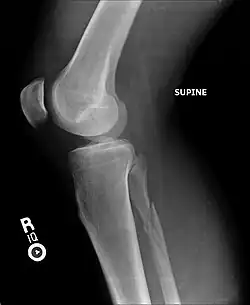

| Radiograph showing a Maisonneuve fracture of the proximal fibula | |

The Maisonneuve fracture is a spiral fracture of the proximal third of the fibula associated with a tear of the distal tibiofibular syndesmosis and the interosseous membrane. There is an associated fracture of the medial malleolus or rupture of the deep deltoid ligament of the ankle. This type of injury can be difficult to detect.[1][2]